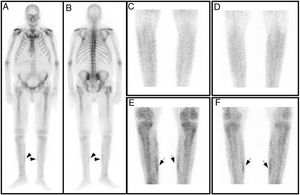

En el estudio planar con difosfonatos no se apreciaron hallazgos gammagráficos significativos en la fase vascular, mientras que, en la fase ósea, se observó una discreta captación del radiotrazador en regiones mediales de las piernas (fig. 1). Este hallazgo fue confirmado por la tomografía computarizada de emisión monofotónica (SPECT), tomografía computarizada de emisión monofotónica/tomografía computarizada (SPECT/TC) (fig. 2) e imagen de reconstrucción 3D (fig. 3), donde se evidenciaron depósitos focales del trazador en partes blandas, en relación con la localización de las lesiones ulcerosas más mediales, confirmando el diagnóstico de calcifilaxis.

Gammagrafía ósea de cuerpo completo anterior (A) y posterior (B). Imágenes planares precoces de piernas (fase vascular) anterior (C) y posterior (D), no evidenciándose hallazgos gammagráficos significativos. Imágenes planares tardías (fase ósea), anterior (E) y posterior (F), se observa mínima hipercaptación del trazador en región medial de ambas piernas.